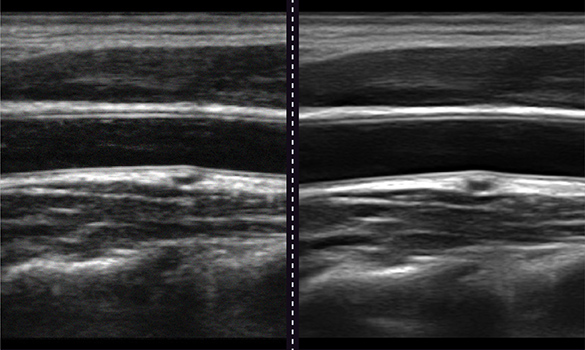

Panoramic Imaging

Allows continuous scanning across large anatomical areas to create a single panoramic image, enabling visualization beyond a single frame and supporting vascular and musculoskeletal evaluation.